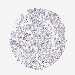

OVARIAN CANCER - Protein expressioni

A mouse-over function shows sample information and annotation data. Click on an image to view it in a full screen mode. Samples can be filtered based on level of antibody staining by selecting one or several of the following categories: high, medium, low and not detected. The assay and annotation is described here.

Note that samples used for immunohistochemistry by the Human Protein Atlas do not correspond to samples in the TCGA dataset.

Antibody stainingi

Antibody staining in the annotated cell types in the current human tissue is reported as not detected, low, medium, or high, based on conventional immunohistochemistry profiling in selected tissues. This score is based on the combination of the staining intensity and fraction of stained cells.

Each image is clickable and will lead to virtual microscopy that enables deeper exploration of all samples and also displays staining intensity scores, fraction scores and subcellular localization as well as patient and tissue information for each sample.

Antibody HPA056632

Staining

High

Medium

Low

Not detected

Intensity

Strong

Moderate

Weak

Negative

Quantity

>75%

75%-25%

<25%

None

Location

Nuclear

Cytoplasmic/membranous

Cytoplasmic/membranous,nuclear

Cystadenocarcinoma, serous, NOS

Cystadenocarcinoma, mucinous, NOS

Carcinoma, endometroid